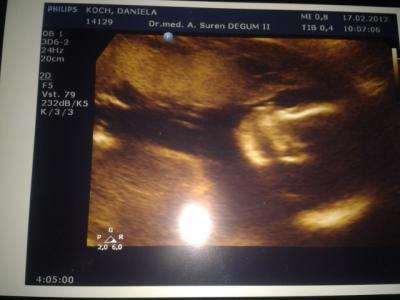

Hi war heute Morgen bei der Feindiagnostik . Alles bestens entwickelt sogar ein paar Tage weiter. Zwerg ist 25 cm und 416 g schwer. Und es wird ein Junge Die ganze Aufregung war umsonst.. Meinen Mann sind die Tränen gekullert beim Outing Und noch ein Gesichtsfoto

Bild zu Zurück von der Feindiagnostig + Outing mega glücklich - Forum für Juli - Mamis